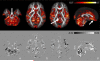

The goal of this study is to characterize the potential effect of artifacts originating from physiological noise on statistical analysis of diffusion tensor MRI (DTI) data in a population. DTI derived quantities including mean diffusivity (Trace(D)), fractional anisotropy (FA), and principal eigenvector (ε(1)) are computed in the brain of 40 healthy subjects from tensors estimated using two different methods: conventional nonlinear least-squares, and robust fitting (RESTORE). RESTORE identifies artifactual data points as outliers and excludes them on a voxel-by-voxel basis. We found that outlier data points are localized in specific spatial clusters in the population, indicating a consistency in brain regions affected across subjects. In brain parenchyma RESTORE slightly reduces inter-subject variance of FA and Trace(D). The dominant effect of artifacts, however, is bias. Voxel-wise analysis indicates that inclusion of outlier data points results in clusters of under- and over-estimation of FA, while Trace(D) is always over-estimated. Removing outliers affects ε(1) mostly in low anisotropy regions. It was found that brain regions known to be affected by cardiac pulsation - cerebellum and genu of the corpus callosum, as well as regions not previously reported, splenium of the corpus callosum-show significant effects in the population analysis. It is generally assumed that statistical properties of DTI data are homogenous across the brain. This assumption does not appear to be valid based on these results. The use of RESTORE can lead to a more accurate evaluation of a population, and help reduce spurious findings that may occur due to artifacts in DTI data.